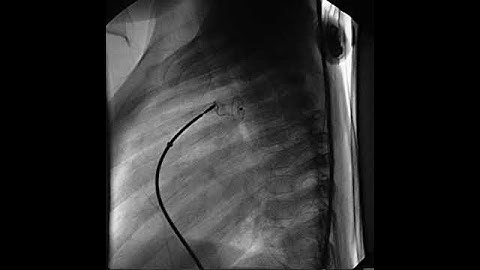

PDA Coil Closure Tiny PDA profiled